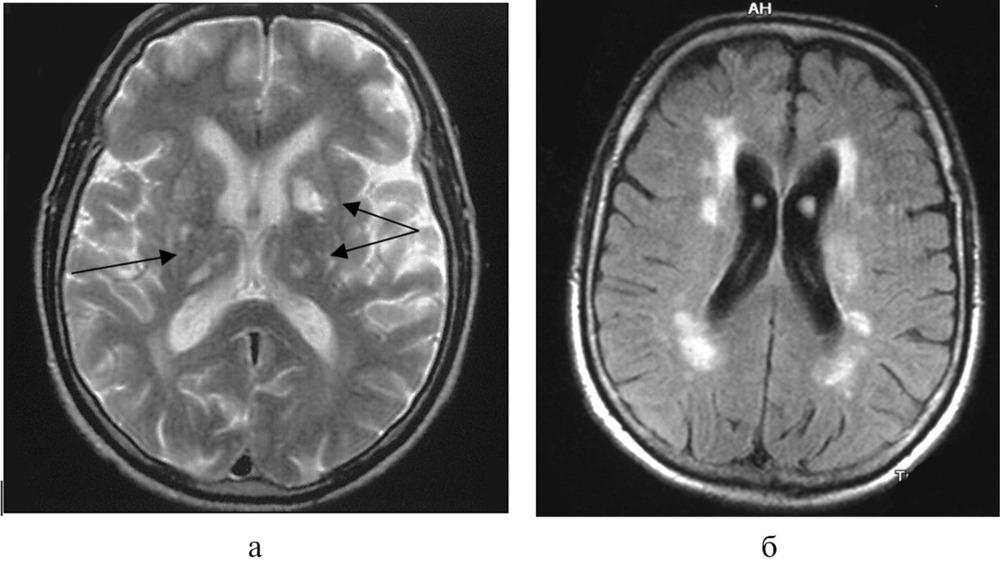

Fazekas grades. Лейкоареоз головного мозга мрт. Перивентрикулярный лейкоареоз мрт. Лейкоареоз Фазекас. Лейкоареоз на кт.

Fazekas grades. Лейкоареоз головного мозга мрт. Перивентрикулярный лейкоареоз мрт. Лейкоареоз Фазекас. Лейкоареоз на кт.

Fazekas grades. Лейкоареоз головного мозга мрт. Перивентрикулярный лейкоареоз мрт. Перивентрикулярный лейкоареоз головного мозга на кт. Лейкоареоз Fazekas 1 что это.

Fazekas grades. Лейкоареоз головного мозга мрт. Перивентрикулярный лейкоареоз мрт. Перивентрикулярный лейкоареоз головного мозга на кт. Лейкоареоз Fazekas 1 что это.

Fazekas grades. Лейкоареоз на кт. Лейкоареоз головного мозга мрт. Перивентрикулярный лейкоареоз. Перивентрикулярный лейкоареоз мрт.

Fazekas grades. Лейкоареоз на кт. Лейкоареоз головного мозга мрт. Перивентрикулярный лейкоареоз. Перивентрикулярный лейкоареоз мрт.